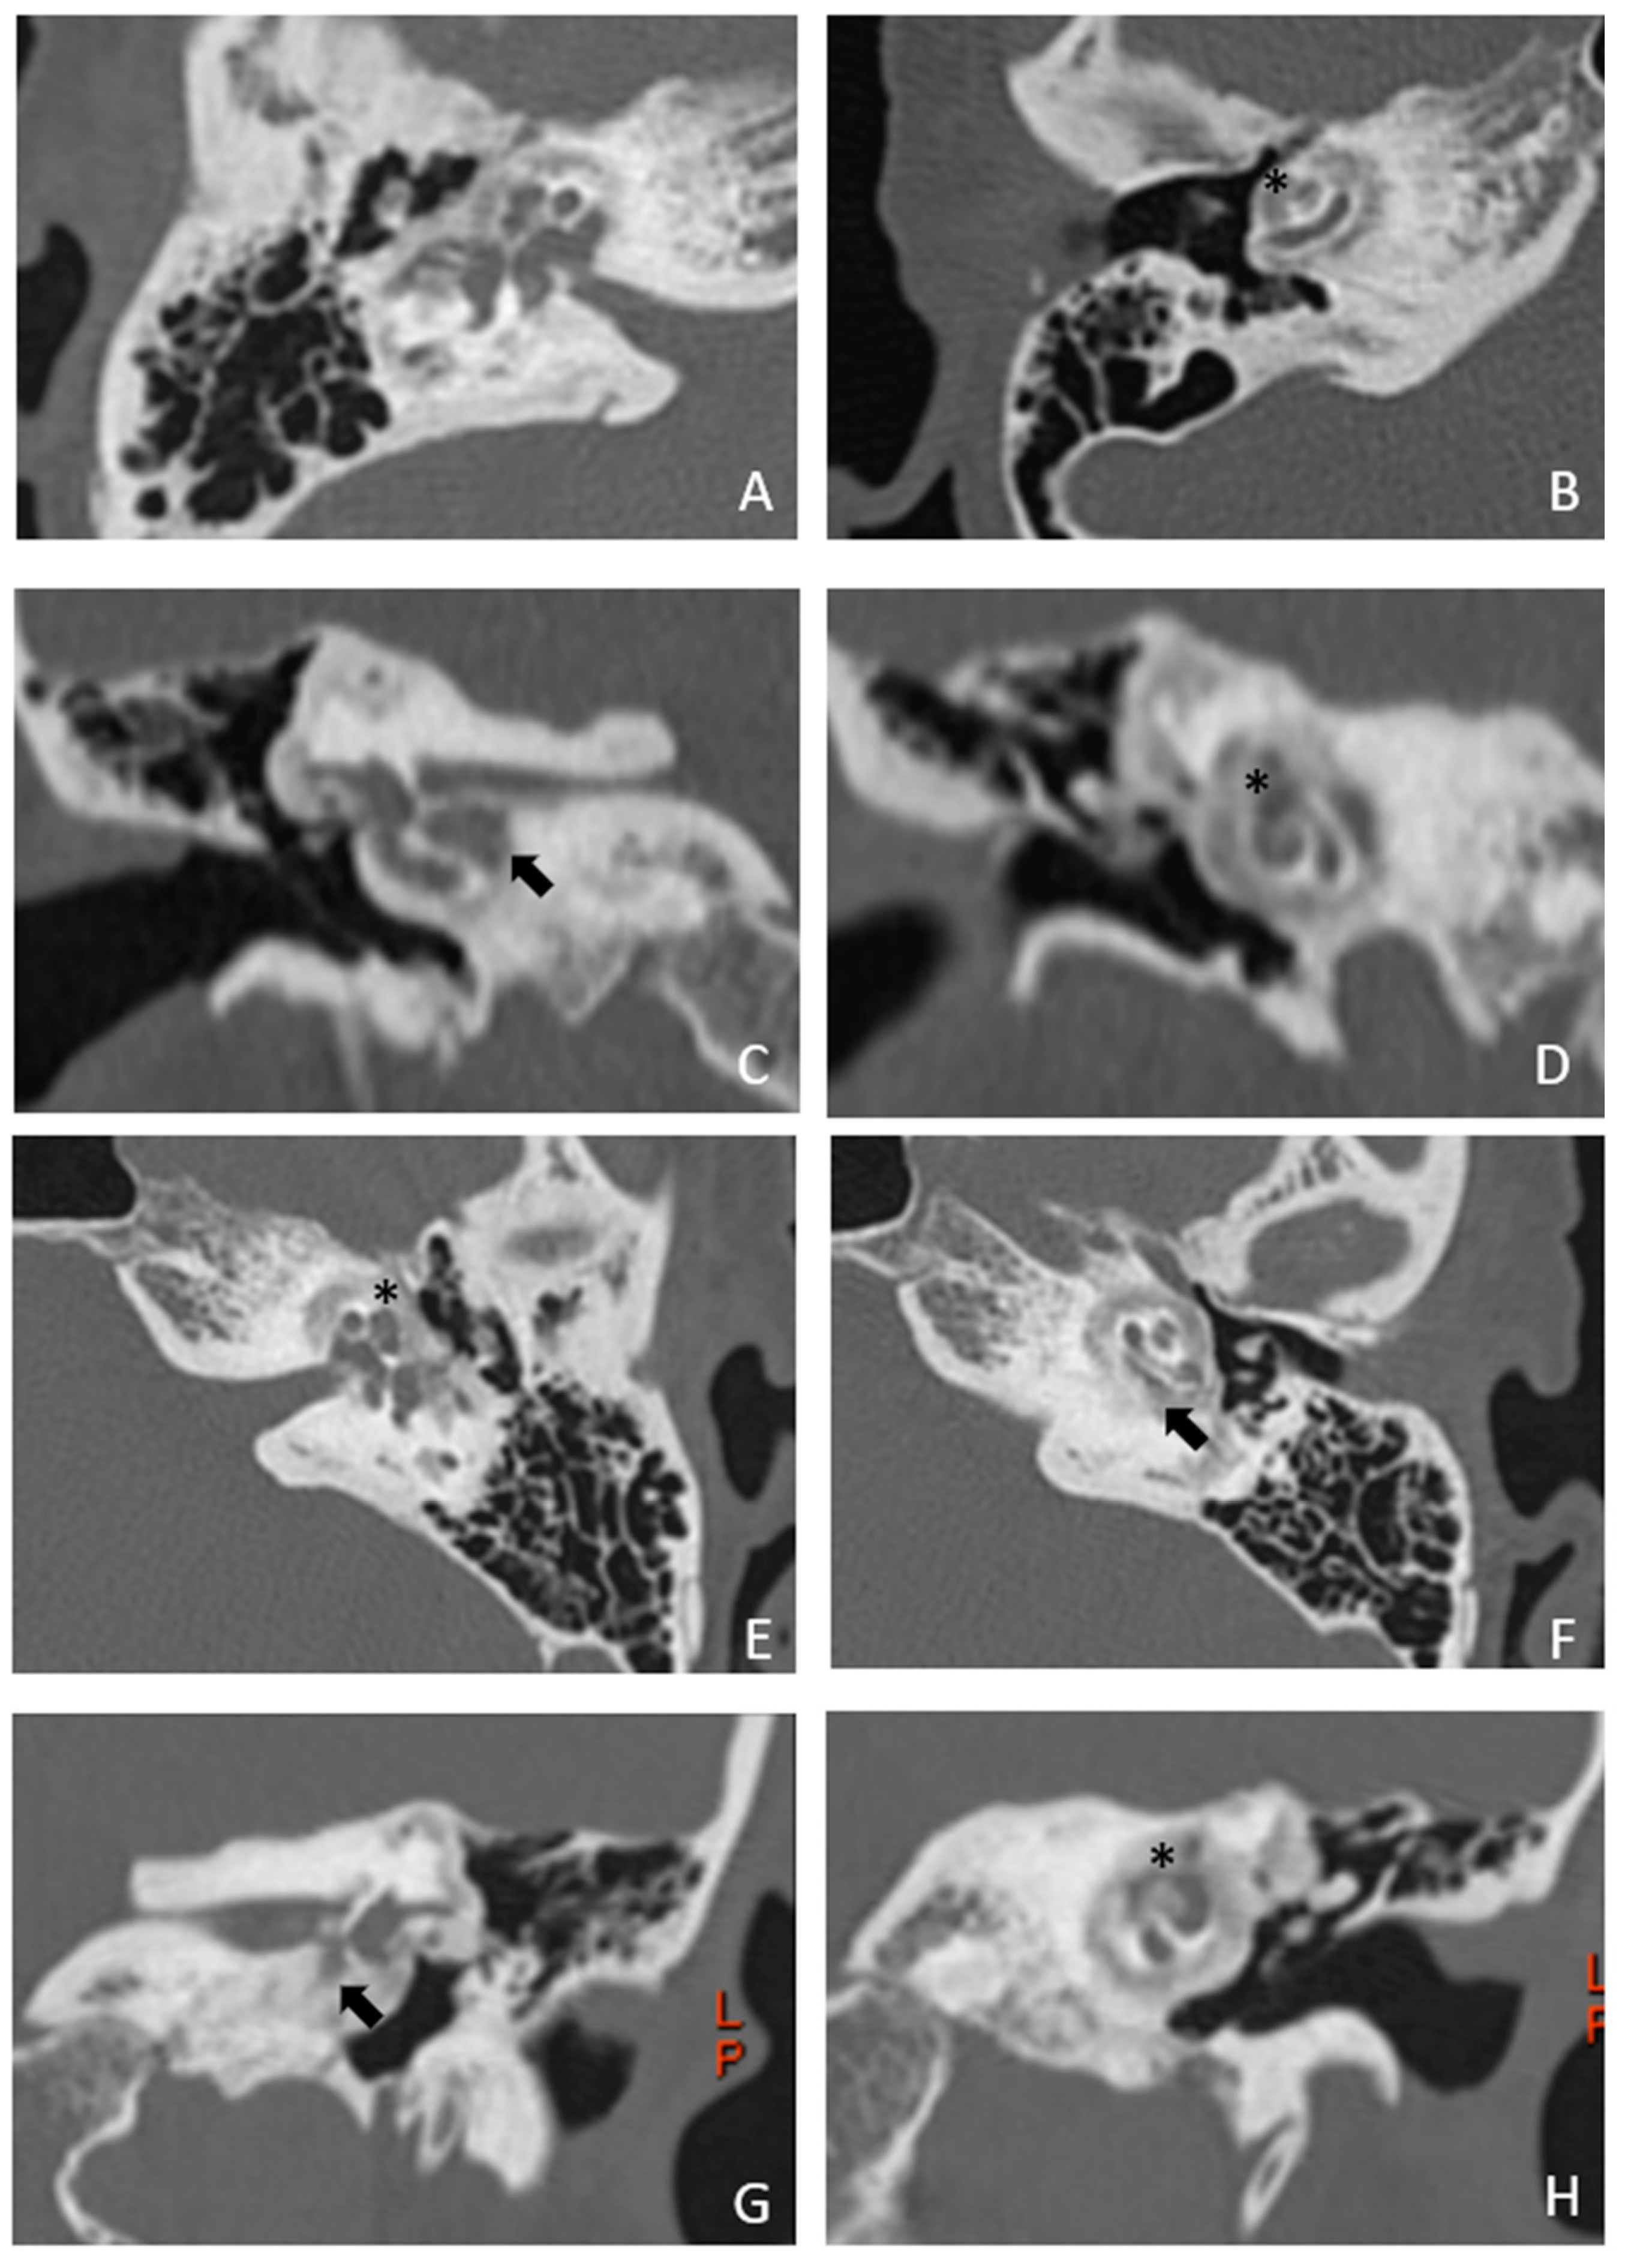

Patient #2, affected by OI: MHL since diagnosis: Bone threshold was similar in both ears, but PTA was worst in the right ear with a larger ABG. HL progressed, but the difference between the two sides was maintained. The patient was fitted with conventional hearing aids bilaterally. Stapes surgery was not performed because of the radiological aspect (Figure 3 and Figure 4): a large cavity is present bilaterally and diffused communication between the cavity and the cochlea is evident.

Figure 4. MR images of patient #2 with osteogenesis imperfecta. MR cisternography: A, axial plane; B, coronal plane. Note the fluid-signal in the newly formed cavities (white asterisk).